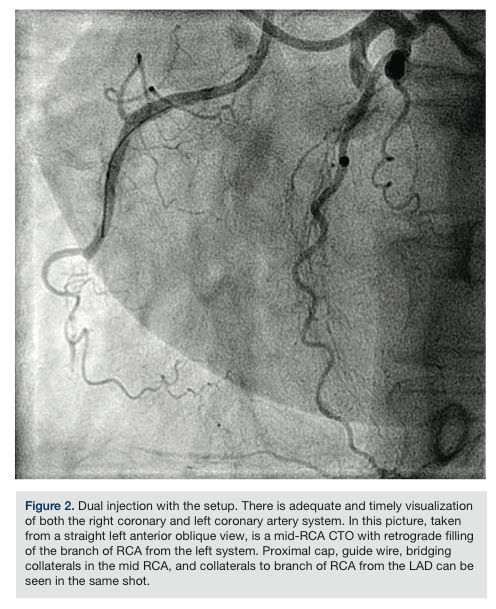

For dual injection: Appropriate settings for injection are dialed into the ACIST injector system. The pressure waves at both the catheters are confirmed individually by turning the stopcocks appropriately. Once it is confirmed that the pressure waves look normal and there is no dampening, the central stopcock is turned down so that it is open to both the ports. The three-way stopcock at site 2 is turned off towards the pressure line so that it is open to flow into the catheter from the connector tube. The injection is performed (Figure 2).

The total volume of contrast used for dual or single injections is displayed at the ACIST screen. During a dual injection, the volume of contrast injected and the pressure of injection from each catheter tip is not the same, as the length of the tubing from the four-way stopcock to each of the coronary catheters is different. However, the difference is insignificant. We attained images with adequate and timely visualization of both the coronary systems using dual injection with this technique

(Figure 2). There was no significant time lag between contrast injections from the ends of the catheters.